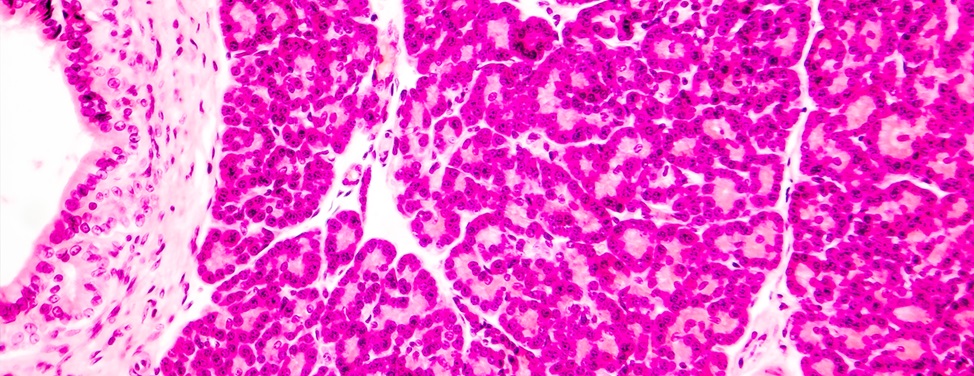

During an islet autotransplant, the patient's own islet cells are isolated from the removed pancreas. They are then put back into the patient, where they start producing insulin. The islet auto-transplant technique is a modification of an islet transplant procedure used to manage severe insulin-dependent (type 1) diabetes, in which islets are isolated from a deceased donor pancreas. In chronic pancreatitis, the patient’s own islets are used, eliminating the risk of tissue rejection.